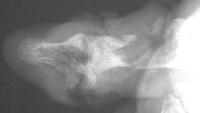

Late Xrays.